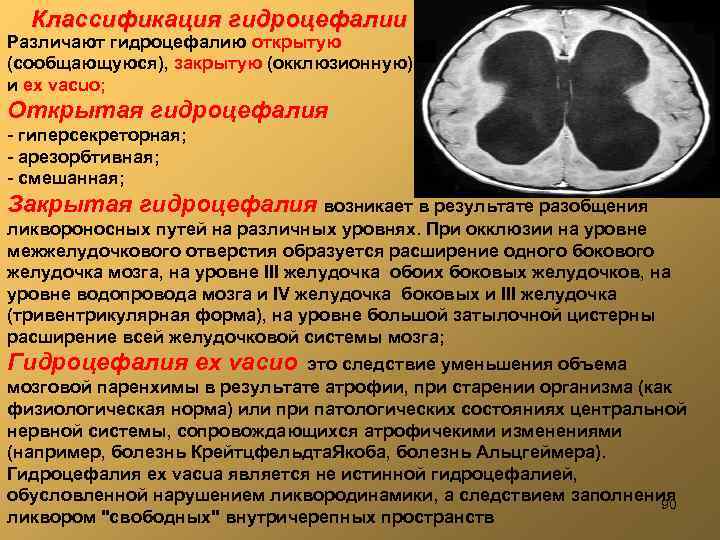

Классификация гидроцефалии Различают гидроцефалию открытую (сообщающуюся), закрытую (окклюзионную) и ex vacuo; Открытая гидроцефалия - гиперсекреторная; - арезорбтивная; - смешанная; Закрытая гидроцефалия возникает в результате разобщения ликвороносных путей на различных уровнях. При окклюзии на уровне межжелудочкового отверстия образуется расширение одного бокового желудочка мозга, на уровне III желудочка обоих боковых желудочков, на уровне водопровода мозга и IV желудочка боковых и III желудочка (тривентрикулярная форма), на уровне большой затылочной цистерны расширение всей желудочковой системы мозга; Гидроцефалия ex vacuо это следствие уменьшения объема мозговой паренхимы в результате атрофии, при старении организма (как физиологическая норма) или при патологических состояниях центральной нервной системы, сопровождающихся атрофичекими изменениями (например, болезнь Крейтцфельдта. Якоба, болезнь Альцгеймера). Гидроцефалия ex vacua является не истинной гидроцефалией, обусловленной нарушением ликвородинамики, а следствием заполнения 90 ликвором "свободных" внутричерепных пространств